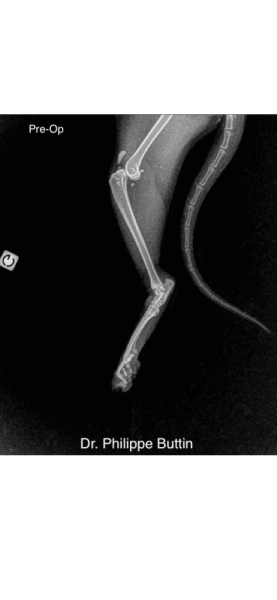

Radiologické snímky